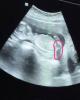

Вот я тоже так думала, но сегодня я увидела отчетливо пирожочек( или это были яйки)))и торчащий писюнчик))